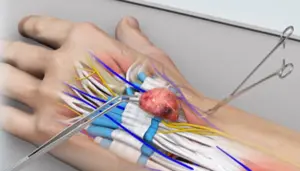

Microsurgical reconstruction involves anastomosis of vessels and nerves less than 2 mm in diameter, often requiring high-magnification optics, specialized micro-instruments, and ultra-fine sutures (9-0 to 11-0 nylon).

Anastomosis Technique: End-to-end vs. end-to-side, interrupted vs. continuous suturing

Image: End-to-end arterial microanastomosis under operative microscope.